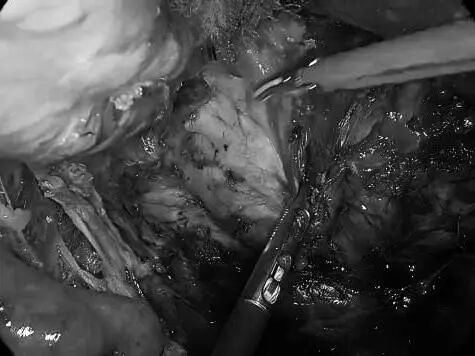

一名女性患者长期受到下腹部坠胀、排便不适等症状困扰,近期发现盆腔内存在肿物,严重影响其生活质量,为寻求进一步诊治,她前往贵州航天医院普外科就诊,经核磁共振(MRI)检查提示:盆腔内直肠与骶骨之间有一个“骶前囊肿”。由于该囊肿位置深,且与周围重要的神经和血管关系密切,若采用传统手术不仅创伤大,还伴随一定的风险。 面对这一棘手难题,普外科立即组织了麻醉科、医学影像科、妇科、重症医学科在内的多学科专家会诊(MDT)。经专家团队详细评估,与患者及家属充分沟通后,为患者制定并成功实施了“腹腔镜下骶前囊肿切除术”。术后恢复良好,不久便康复出院。 【疾病科普|什么是骶前囊肿?】 骶前囊肿,可以理解为生长在骨盆最深处、直肠后方的一个囊性肿物。由于它“躲藏”的位置非常特殊,四周紧邻着控制排便和感觉的重要神经与血管,因此被视为盆腔外科手术中的一个难点。 它可能带来哪些影响? 1.随着囊肿逐渐增大,可能会压迫直肠,引起排便困难或坠胀感。 2.压迫骶神经,可能导致腰骶部或会阴区的酸胀、疼痛。 3.囊肿本身也可能发生感染,形成脓肿,加重不适。 【技术介绍|腹腔镜下骶前囊肿切除术】 对于骶前囊肿这类较深的病灶,腹腔镜下骶前囊肿切除术提供了一种更为微创、便于操作的解决方案。 它是如何进行的? 医生仅通过腹部几个约0.5-1厘米的小孔,其中一个孔放入带高清摄像头的腹腔镜,将盆腔内的景象放大并清晰地投射到屏幕上,如同给了医生一双进入体内的“眼睛”。其他几个小孔则伸入细长的专用手术器械。医生看着屏幕,遥控这些器械,在清晰的视野下精细地分离并完整切除囊肿。 腹腔镜微创手术的特点包括: ▶创伤较小:避免了传统手术的长切口,体表疤痕小。 ▶视野清晰:放大后的图像让医生能更清楚地分辨囊肿与周围重要结构。 ▶操作精准:有助于更完整地切除囊肿,并尽力保护盆腔神经功能。 ▶恢复较快:因手术创伤小,患者术后疼痛感更轻,下床活动早,住院时间也可能缩短。 注:本文旨在进行健康科普,分享医疗案例与科普知识,不能替代任何专业的医疗建议。如有任何健康问题,请务必及时咨询并遵从专业医生的诊疗意见。 贵州航天医院普外科专家简介 高大勇 普外科(肛肠外科)学科带头人、名誉主任,主任医师、教授 临床擅长:对中西医结合诊治肛肠学科各种常见病、多发病及疑难杂症等具有丰富的临床经验。 原遵义市第一人民医院(遵义医科大学第三附属医院)、遵义市中医院肛肠科主任。中华中医药学会肛肠分会常委,全国中医肛肠学科名专家,中国健康促进与教育协会肛肠分会常委,中国康复医学会肛肠疾病康复专业委员会常委,中国民间中医医药研究开发协会肛肠分会副秘书长,中国医师协会中西医结合肛肠医师专业委员会常委,国家二级心理咨询师,贵州省第一批中医名医工作指导老师,遵义市名中医,遵义市肛肠学会会长,遵义市肛肠质控中心名誉主任,遵义市中西医结合学会名誉会长,遵义市健康科普专家,原贵州省中西医结合学会肛肠分会副主任委员、贵州省中医肛肠质控中心副主任、遵义市医学会医疗鉴定委员会专家、遵义市卫生系列高级评委。发表论文30余篇,主编和参编医学著作5本,主持省级科研课题2项、市级科研课题2项、院级科研课题1项。 梁 跃 普外科党支部书记、主任,主任医师 临床擅长:对普外科各类肿瘤手术具有丰富的临床经验。 毕业于遵义医学院,遵义市医学会小儿外科学分会常务委员,遵义市肛肠协会理事,遵义市医学会核医学分会(第二届)委员会委员;荣获第三期“黔医人才计划”优秀学员称号;主持市级课题1项,完成省级课题1项,在国内各类刊物上发表论文10余篇。 钱科洪 民盟盟员,普外科副主任医师 临床擅长:从事普外科临床工作30余年,对各类普外科疾病的诊治、乳腺、甲状腺、胃十二指肠、结直肠等疾病及疑难杂症具有丰富的临床经验。 毕业于遵义医学院临床医疗系,2009年前往中山大学附属第一医院微创外科进修学习,在国内各专业期刊发表论文数篇。 贵州航天医院普外科简介 基本情况 贵州航天医院普外科成立于1968年,前身属于原航天部O61基地3417医院外一科,1998年3417医院、3427医院合并后更名为普外科,下设胃肠外科、肛肠外科2个亚专业科室,拥有在全市较为先进的专科设备和技术,是中国疝病专科联盟单位,贵州医科大学附属医院胃肠外科专科联盟单位。开放床位40张,配备医护人员21人。 专科特色 普外科致力于胃肠及肛肠疾病的外科临床诊治及科研,以腹腔镜微创外科技术为本,形成以快速康复治疗胃肿瘤、结直肠肿瘤、小肠肿瘤、直肠脱垂、肥胖病、急腹症、各类疝、痔、瘘等专科特色,同时注重胃肠疾病尤其是结直肠恶性肿瘤的基础研究和临床转化研究,总体诊断和治疗水平在区域同级医院居于领先水平。 开展手术:腹腔镜下胃癌根治术,腹腔镜下袖状胃切除术,腹腔镜下胃肠道间质瘤切除术,腹腔镜下结、直肠癌根治术,胃癌、结直肠癌的精准治疗,腹腔镜下小儿疝气、成人疝修补术,腹腔镜下阑尾手术,内痔的硬化注射治疗及痔疮的微创治疗:ATH、PPH、TST,直肠脱垂的各种手术治疗,难治性伤口VSD技术,鼻胃肠管、肠梗阻导管置入术,肛肠术后间歇性导尿技术,并引进了中医适宜技术,也为各种化疗患者提供输液港安装,提高患者就医体验。 腹腔镜下腹股沟疝 无张力修补术 腹股沟疝里金斯坦 (Lichtenstein)手术 PPH微创术治疗环状混合痔 黏连性或炎性肠梗阻-肠梗阻导管 腹腔镜袖状胃切除 腹腔镜阑尾切除术 腹腔镜阑尾肿瘤切除术 腹腔镜下结肠癌根治术 诊疗范围 胃肿瘤、结直肠肿瘤、小肠肿瘤、肥胖症、各类急腹症、腹部外伤、腹壁疝、便秘、直肠脱垂、痔疮、肛瘘、肛裂等胃肠、肛肠外科疾病。 END